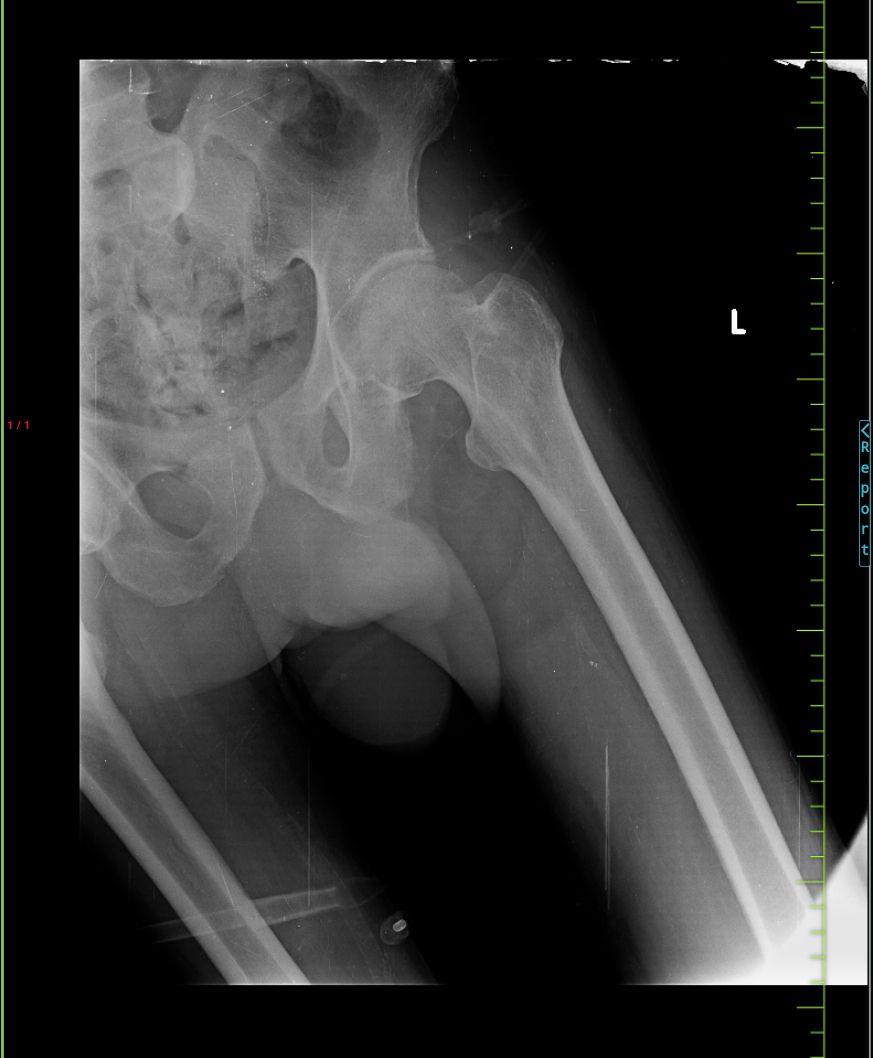

There was H/O Giddiness, H/O Fall (Twice), H/O Loss of Consciousness for 5 min.

Patient has a History of fall in the Bathroom one week ago.

X- Ray C - Spine

X-Ray